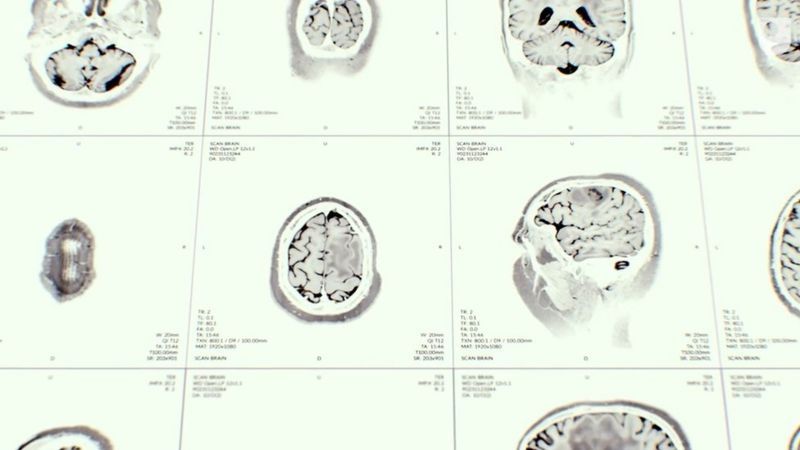

Un psiquiatra la examinó y ordenó una resonancia magnética.

En ese examen, los médicos encontraron un quiste en su cerebro y fue remitida a urgencias para que le hicieran más estudios.

"Cuando llegué a urgencias, revisaron el quiste y dijeron que probablemente había nacido con él, que quizás no tenía nada que ver con los síntomas".